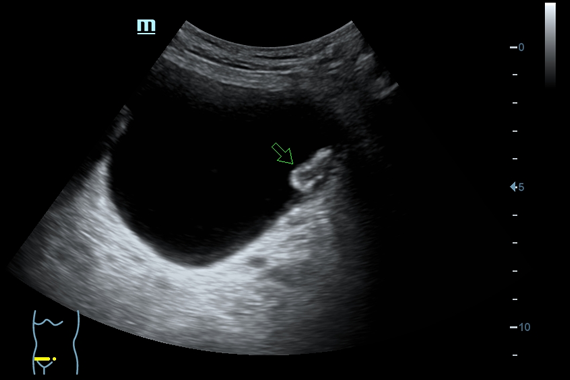

Система ультразвукового исследования Mindray DC-60 EXP X-INSIGHT является новейшей разработкой для проведения комплексных обследований на высшем уровне. Она обеспечивает решение самых сложных задач в таких областях, как кардиология, акушерство и гинекология, сосудистые заболевания, педиатрия и многие другие.

DC-60 EXP X-INSIGHT - это современный стационарный УЗИ-аппарат с функцией сенсорного управления и очищенной гармонической визуализацией, обеспечивающей лучшее контрастное разрешение и технологию 4D-визуализации. Он оснащен 21,5-дюймовым монитором, который может поворачиваться на 180 градусов, что удовлетворяет потребности врачей в качественной ультразвуковой диагностике.

• Gynecology package - предустановленные параметры, аннотации, маркеры, программы измерений для гинекологии

• Внутриполостной датчик Mindray V11-3

• Ректально-вагинальный датчик Mindray V11-3B